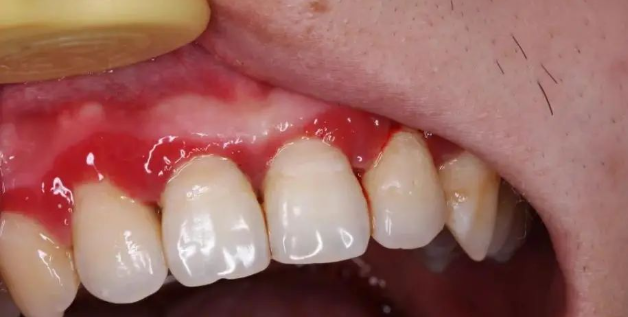

牙周炎一开始出现的症状是:牙龈发红,刷牙时有点出血,啃一口苹果后发现留下一圈血印子。

如果不在意,牙龈开始退缩,牙齿缝显露出来。